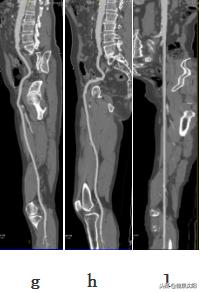

ghl:显示下肢血管曲面、拉直影像